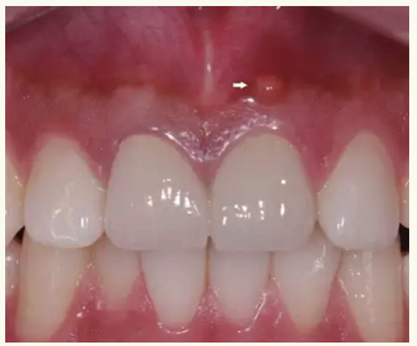

▲ 術(shù)前,21唇側(cè)牙齦距離齦緣2mm處及瘺管

▲牙膠尖示蹤顯示瘺管與此相通